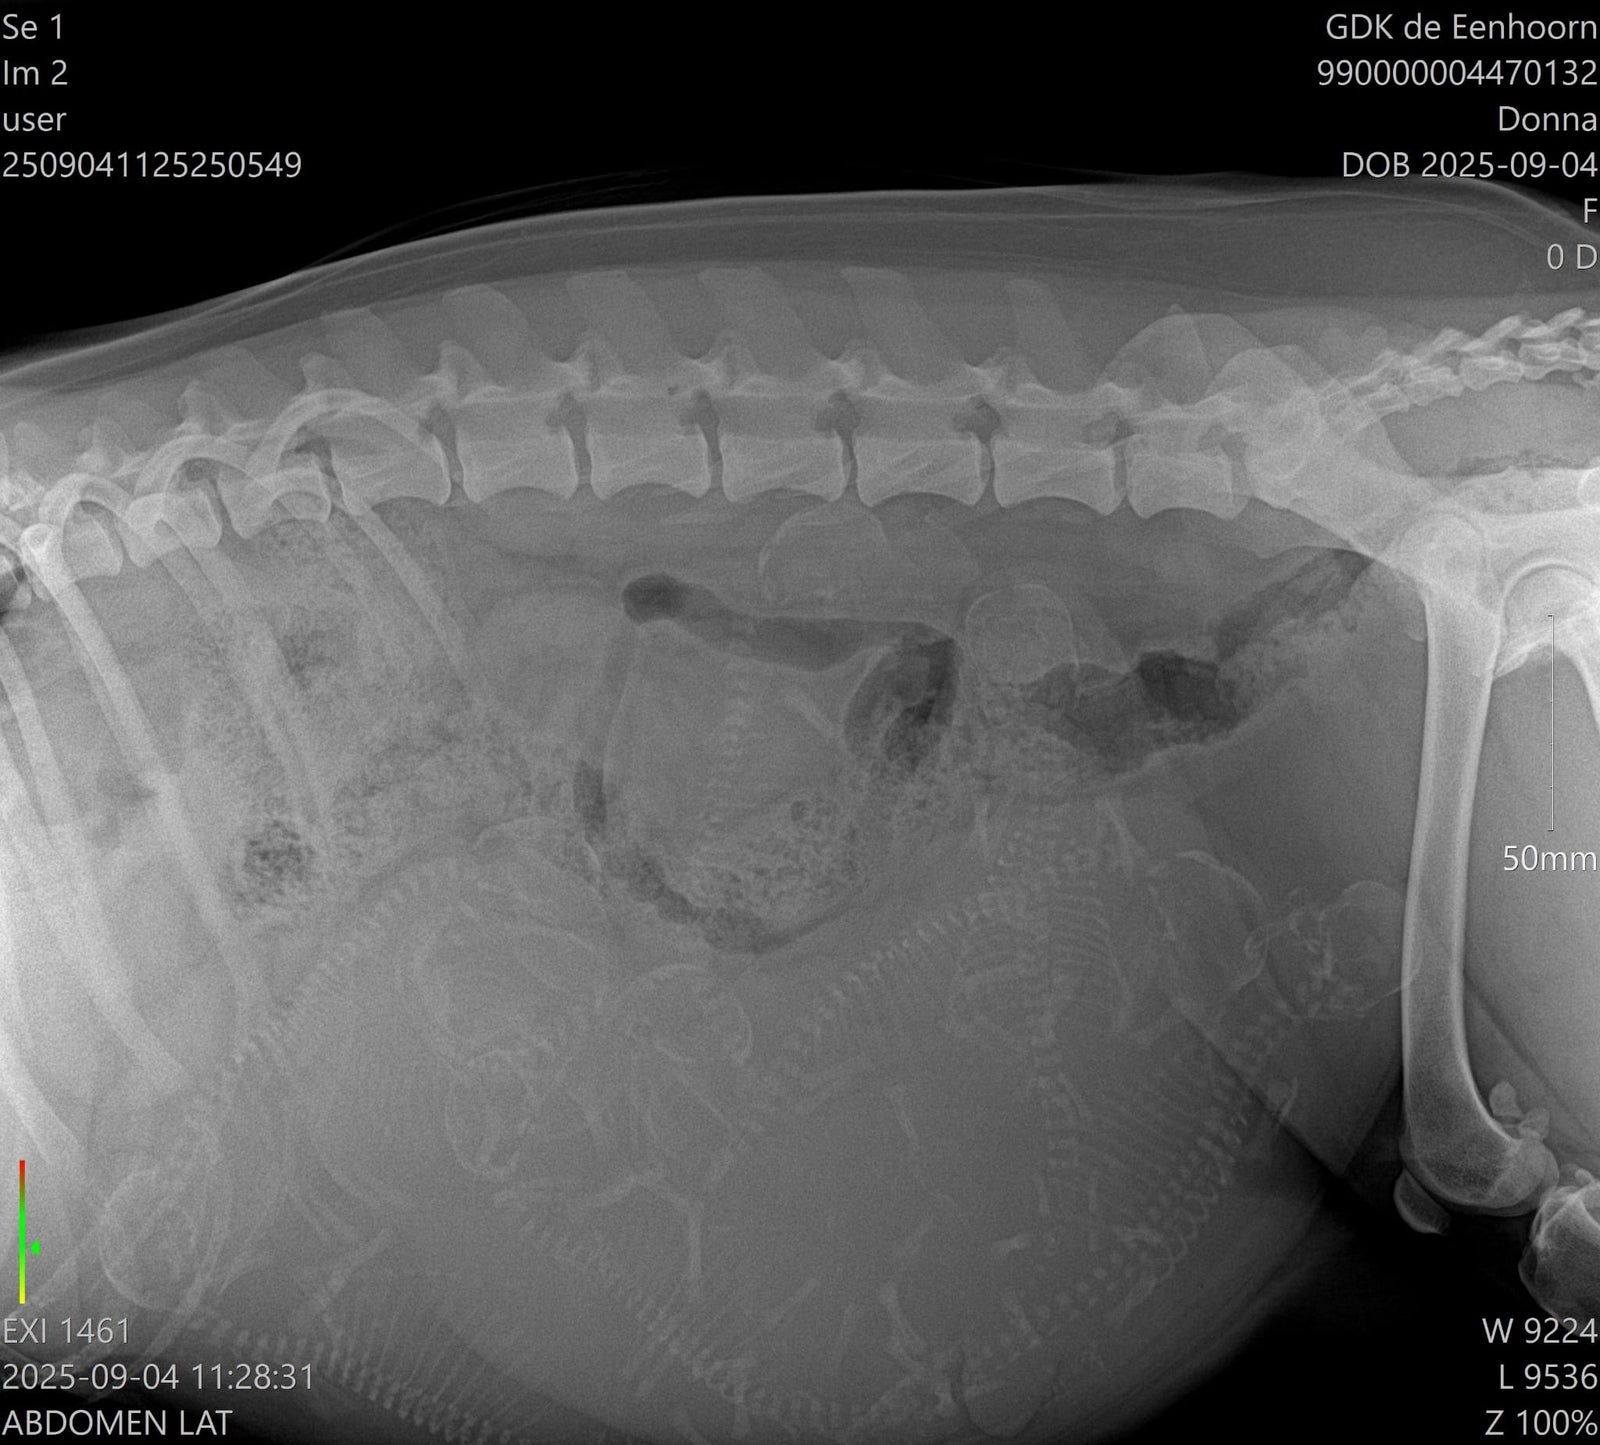

Een röntgenfoto volgt binnenkort, zodat we een beter beeld krijgen van het aantal pups.

Echo en röntgen-foto!